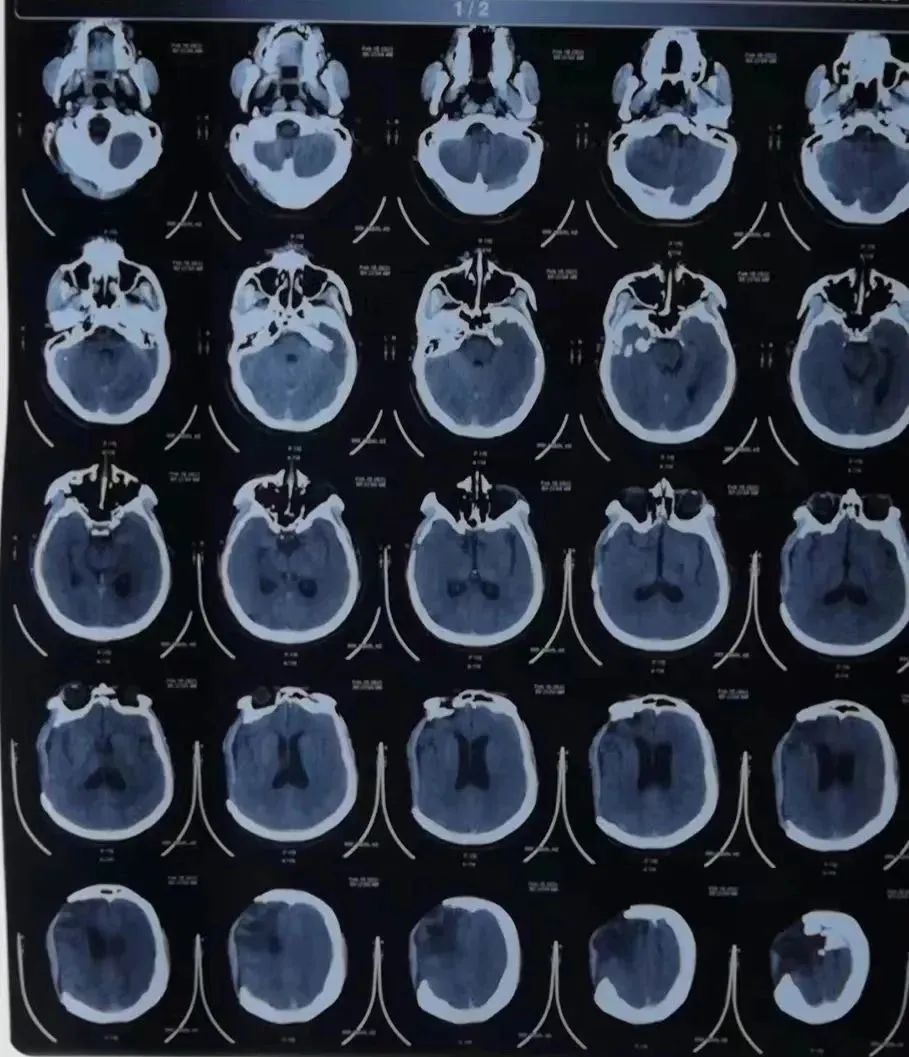

开放性重度颅脑损伤、颅骨开放粉碎凹陷性骨折、右额叶多发脑挫裂伤、右额顶部急性硬膜下血肿......

今年19岁的小王骑电动车时不慎与汽车相撞,头部流血不止,120接来我院,入院时已经陷入昏迷,前额部有一15cm长裂口,颅骨粉碎,且有部分脑组织流出,病情危重,随时有生命危险,病情十分危重,需立即行手术治疗。

(术前影像报告)

考虑上矢状窦破裂,病情非常凶险,神经外科吕松林主任立即带领团队为患者完善各项术前准备,积极准备手术治疗。同时与麻醉科、手术室、输血科紧密沟通,保障患者顺利通过绿色通道进行救治。

由于上矢状窦由纤维组织构成,弹性差、管壁薄、支撑力差、损伤后不易回缩,故出血难止,于是神经外科团队组织进行多次进行讨论、研究,制定了周密的手术方案,确保手术顺利进行。

(术后影像报告)

手术过程一切顺利,止住了静脉窦的出血,清除了脑内血肿。术后十天患者意识逐渐恢复,一个月后康复出院。三个月后顺利完成颅骨修补。